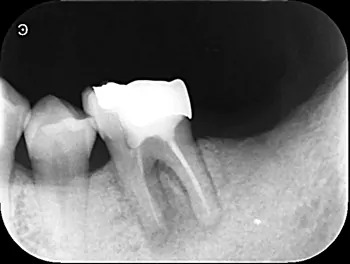

治療前

| 治療説明 | 当院でレントゲン撮影をすると左下の奥歯の根の先に黒く透過像を認めました。歯周病の検査も行いましたが、問題は認められず、根の先の問題だけだった為、残せる可能性が高い事を説明しました。 |